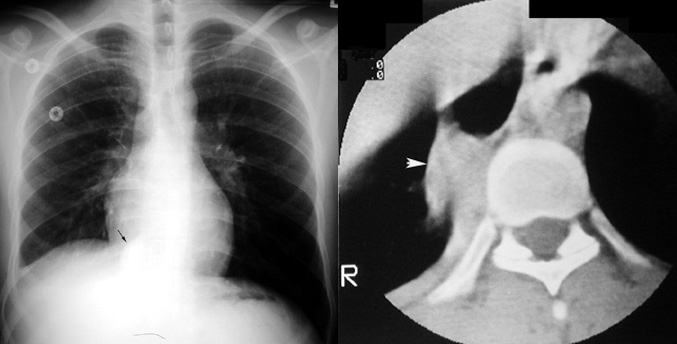

Mycobacterium Marinum